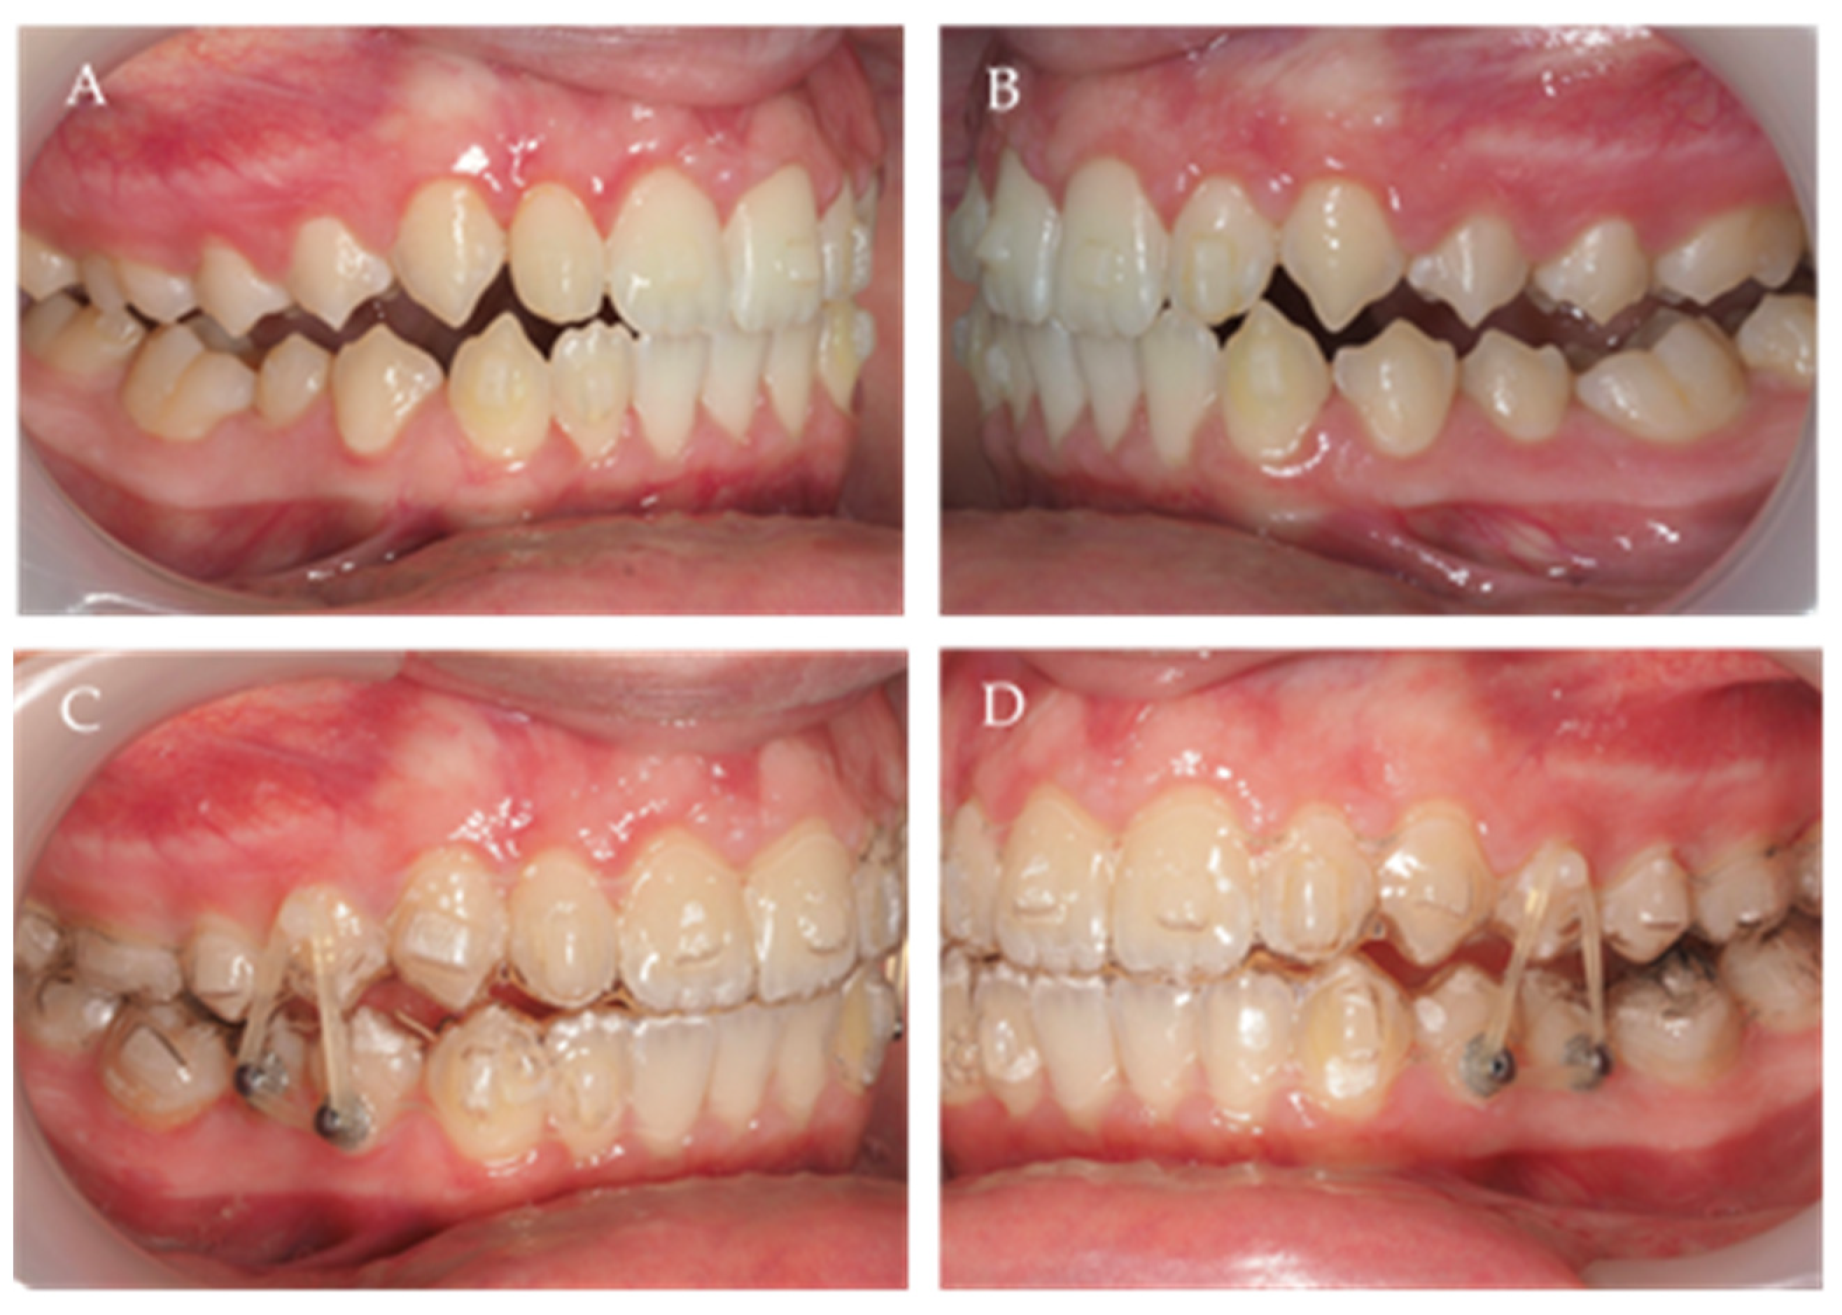

Scissor Bite Occlusion . 1, 2, 3 brodie first. The patients selected for this experiment were 14 years of age or older, at which time the patients had completed establishing. B, at 2 months of treatment, miniscrews were bilaterally placed. Scissor bite can be described as a malocclusion in which the mandible arch was contracted within the maxillary arch. A, start of improvement of maxillary left second molar scissors bite; However, the occlusal factors such as. Scissor bite (sb.) is a rare malocclusion that is challenging to diagnose and is often associated with a retrognathic. Scissor bite, a buccal crossbite, is an uncommon malocclusion affecting between 1.0 % to 1.5 % of the population. This paper describes the use of a modified tpa and cantilever springs to correct the scissor bite of the maxillary second molars, eliminating the need for comprehensive orthodontic. Bilateral buccal scissors bite itself might not directly lead to a pathological condition;

Scissor Bite Occlusion This paper describes the use of a modified tpa and cantilever springs to correct the scissor bite of the maxillary second molars, eliminating the need for comprehensive orthodontic. Bilateral buccal scissors bite itself might not directly lead to a pathological condition; Scissor bite, a buccal crossbite, is an uncommon malocclusion affecting between 1.0 % to 1.5 % of the population. Scissor bite (sb.) is a rare malocclusion that is challenging to diagnose and is often associated with a retrognathic. This paper describes the use of a modified tpa and cantilever springs to correct the scissor bite of the maxillary second molars, eliminating the need for comprehensive orthodontic. Scissor bite can be described as a malocclusion in which the mandible arch was contracted within the maxillary arch. 1, 2, 3 brodie first. The patients selected for this experiment were 14 years of age or older, at which time the patients had completed establishing. A, start of improvement of maxillary left second molar scissors bite; However, the occlusal factors such as. B, at 2 months of treatment, miniscrews were bilaterally placed.